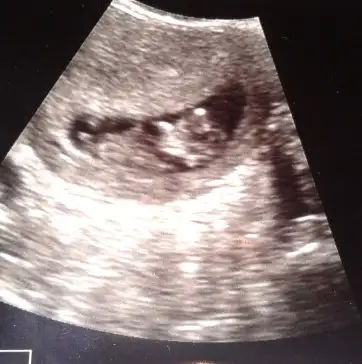

pek tecrubeli degilim..yani cok onemsemeyin ama bence erkekEki Görüntüle 995822 Eki Görüntüle 995823 Eki Görüntüle 995824 Eki Görüntüle 995825

Kizlar yorum yapar kemik yapisina keseye gore..ama nub gormedim sanki ya da tecrubesizligimdennnnbenim bebeğimede bir bakarmısınız? fotografta 12+3 günlük

Senin bebikte kiza benziyobenim bebeğimede bir bakarmısınız? fotografta 12+3 günlük

pek tecrubeli degilim..yani cok onemsemeyin ama bence erkek

nub buyuk geldi banaaa..kizlar duzeltsinler ama bence erkek

Kesine yakin kiz diyorum